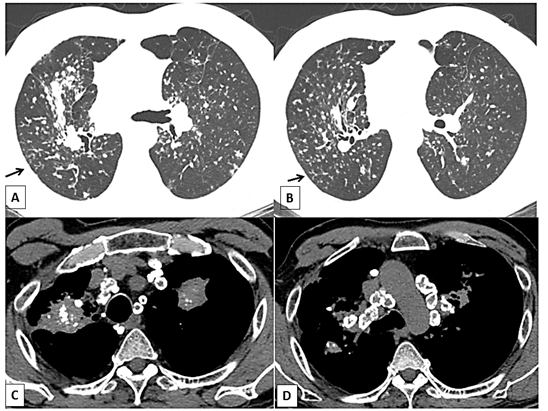

Leukogram and biochemistry showed normal results except elevated C-reactive protein. Computed tomography showed diffuse interstitial pattern, with small nodules and conglomerated masses in the upper lobes of both lungs. Hilar and mediastinal lymph nodes were enlarged with extensive calcification, with the characteristic eggshell pattern. In addition, the tree-in-bud sign was more observed in right upper lobe of the lung (Figure 1).

Simple silicosis is radiologically characterized by the presence of bilaterally symmetrical  micronodular interstitial infiltrates, predominantly in upper lobes. These nodules have a centrilobular pattern of distribution, but may also have a perilymphatic distribution. The presence of small airway filling, with images of a tree-in -bud, is not characteristic of simple silicosis and should always suggest an associated mycobacterial infection, as demonstrated in the case presented (Figure 1).7,18,20

Figure 1 Typical case of complicated silicosis (massive progressive fibrosis) in a 60-year-old man. (A) and (B) High resolution tomography scan of the chest (window of parenchyma): presence of small nodules and opacities in the posterior of the upper lobes. (arrows): Tree-in-bud pattern. (C) Mediastinal window illustrating a conglomerated mass with punctiform calcifications in the posterior region of the upper lobes, and adjacent pleural thickening of the right lung and the calcifications of the lymph nodes. (D) Mediastinal window illustrating egg-shell-type calcifications on the periphery of the lymph nodes.